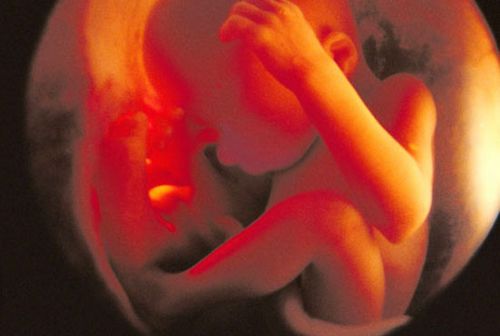

Календар вагітності по тижнях і місяцях

Календар вагітності по тижнях

На нашому сайті для мам ви знайдете календар вагітності. У ньому по тижнях буде розписано, що відбувається всередині вас, а також наведено список порад і рекомендацій, на що слід звернути увагу.

Як тільки ви завагітніє, ваш малюк почне рости і з зовсім мікроскопічного зародка за кілька місяців перетвориться в карапуза зростом близько півметра. Темпи його зростання в багато разів перевищують ваші темпи зростання під час вагітності.